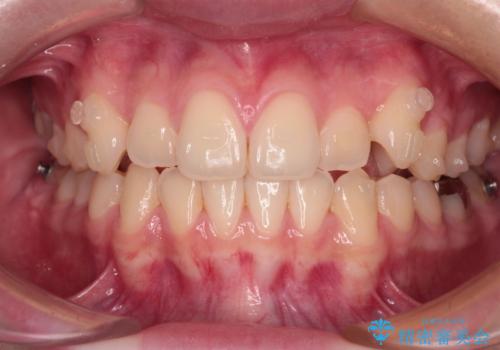

- 左右の八重歯を気にして来院された患者様です。

歯列としてはインビザラインでもワイヤー矯正でも対応できるものでしたが、インビザラインによる治療を希望されていました。

上顎の八重歯改善にインビザラインでは時間のかかってしまう可能性があり、更には口元が治療前よりも突出してしまう可能性があったため、補助装置により八重歯を事前に引き込んでおくことで、インビザラインによる治療をスムーズに行えるように計画しました。

補助装置を使用したことで、口元が突出することもなく、スムーズに仕上げることができました。